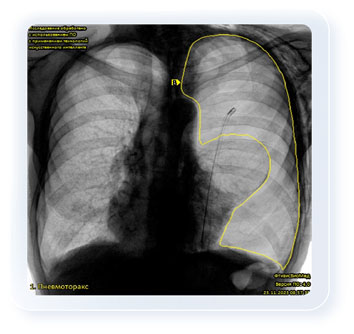

Dịch vụ FthizisBioMed cung cấp khả năng chẩn đoán tự động các bệnh lý của cơ quan lồng ngực như: lao, ung thư, bệnh tim mạch, COVID-19 và các bệnh khác với độ chính xác rất cao. Thời gian phân tích một ảnh chụp X-quang hoặc phim chụp huỳnh quang của dịch vụ FthizisBioMed là 0,8 giây.

Dịch vụ có thể được sử dụng dưới hình thức điện toán đám mây. Điều này có nghĩa là bất kỳ bác sĩ X-quang nào tại bệnh viện ở Việt Nam đều có thể, từ thiết bị X-quang của mình, gửi hình ảnh chụp qua internet lên nền tảng đám mây và trong vòng 15–20 giây sẽ nhận được các khuyến nghị chẩn đoán từ dịch vụ FthizisBioMed cho bệnh nhân của mình.